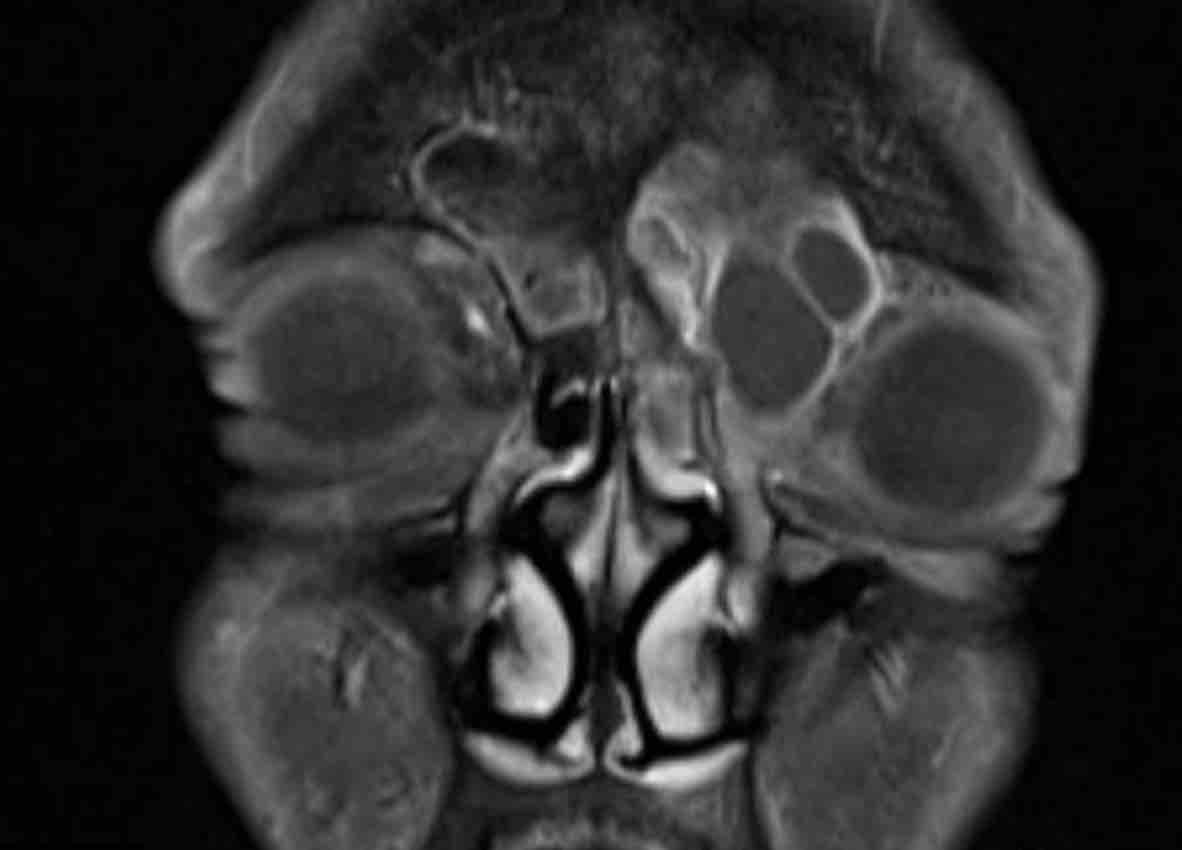

Các hình ảnh này của một bệnh nhân nam 16 tuổi với biểu hiện lồi mắt và chảy máu mũi.

Trên các hình ảnh này, có một tổn thương phá hủy xương với xâm lấn vào hốc mắt.

MRI cho thấy một khối u phá hủy một bên với hạn chế khuếch tán rõ rệt (giảm tín hiệu trên bản đồ ADC).

Như vậy, chúng ta có ba dấu hiệu cảnh báo.

Hạn chế khuếch tán là một lập luận khác chống lại chẩn đoán u xơ mạch máu vị thành niên, vì một tổn thương mạch máu sẽ không gây ra hạn chế khuếch tán.

Có xâm lấn vào hốc mắt và cả vào phần mềm phía trước của má (mũi tên).

Sinh thiết được thực hiện và cho kết quả là u cơ vân (rhabdomyosarcoma), được điều trị bằng hóa trị liệu.